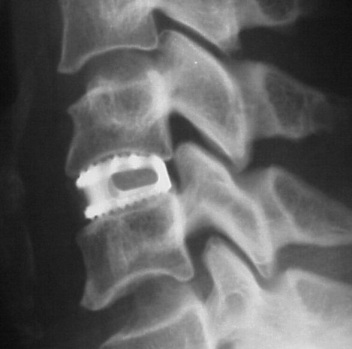

Ejemplo de caja.

Resultados del sistema Cespace. La imagen de la izquierda del montaje superior que aparece a continuacion corresponde a una caja Cespace insertada dos semanas antes. La imagen de la derecha, en la que pueden observarse evidentes puentes oseos corresponde a una caja que fue colocada nueve meses antes de la radiografia. Los resultados en cuanto a estabilizacion primaria y secundaria son excelentes.